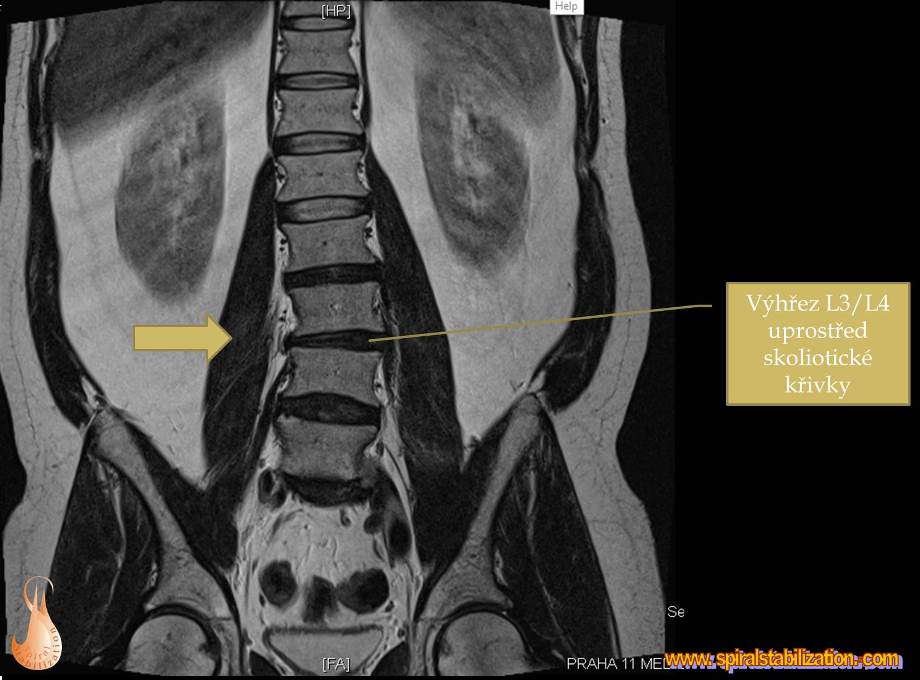

Výsledky hernia L3/L4